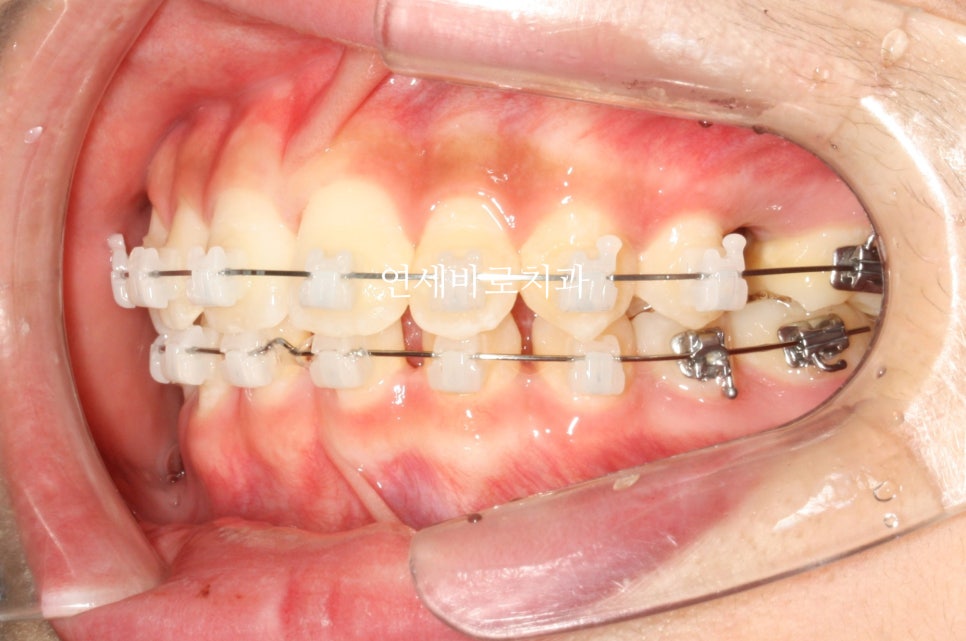

이 친구는 약간의 돌출도 보이고 있었기 때문에 위쪽 치아를 두개 발치했었습니다.

약2년의 치료기간이 걸렸으며 올해 초에 정기검진을 왔습니다

치료가 끝난지 약 3년정도 지난 모습인데 긴밀한 교합으로 인해 치료결과가 잘 유지되고 있는 것 같습니다.